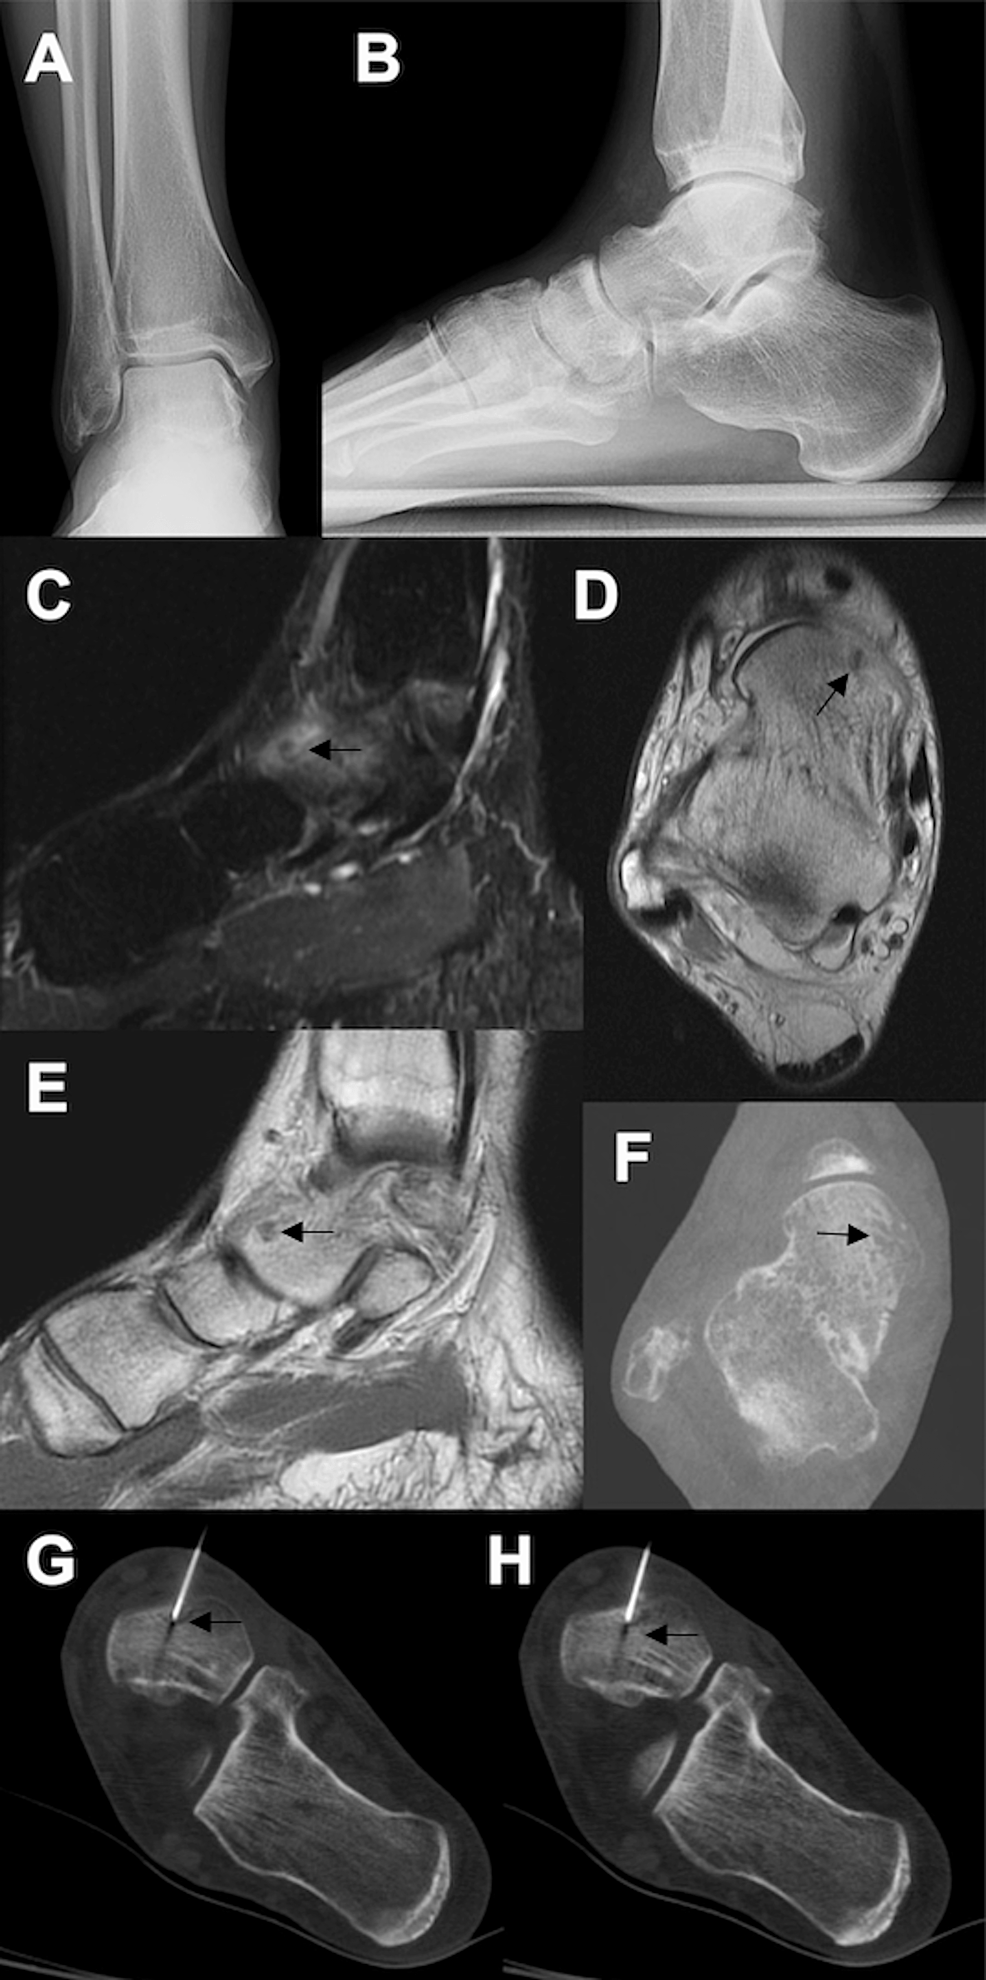

Cureus Osteoid Osteomas of the Talus A Case Report of Four Patients Osteoid Osteoma Dental osteoid osteoma, by contrast, is commonly located within cortical bone. osteoid osteoma is characterized by an intracortical nidus with a variable amount of calcification, as well as cortical thickening,. index institute of dental sciences indore. Satish karandikar 1, gagan thakur 1, manisha tijare 2, shreenivas k 2, kavita agrawal 3. osteoid osteoma of mandible. Herein, we. Osteoid Osteoma Dental.